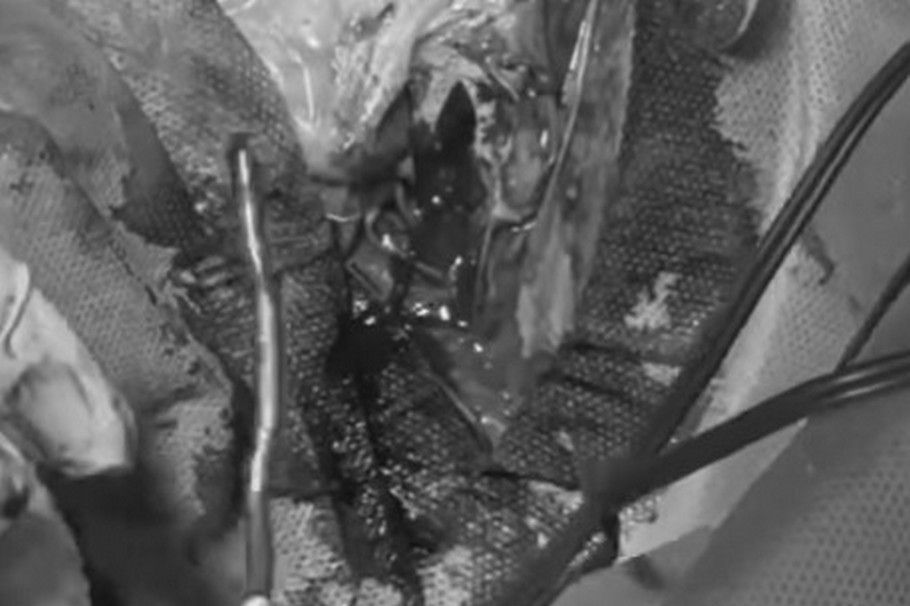

У лікарні Дніпра з голови пораненого воїна дістали чужорідне тіло довжиною до 10 см

Нейрохірурги Мечникова видалили чужорідне тіло довжиною до 10 см в правій скроневій ямці.

Кілька годин професор Андрій Сріко, лікар Микита Гулідин, анестезіолог Петр Голота робили доступ під мікроскопом, щоб витягнути відламок, який забирав життя.